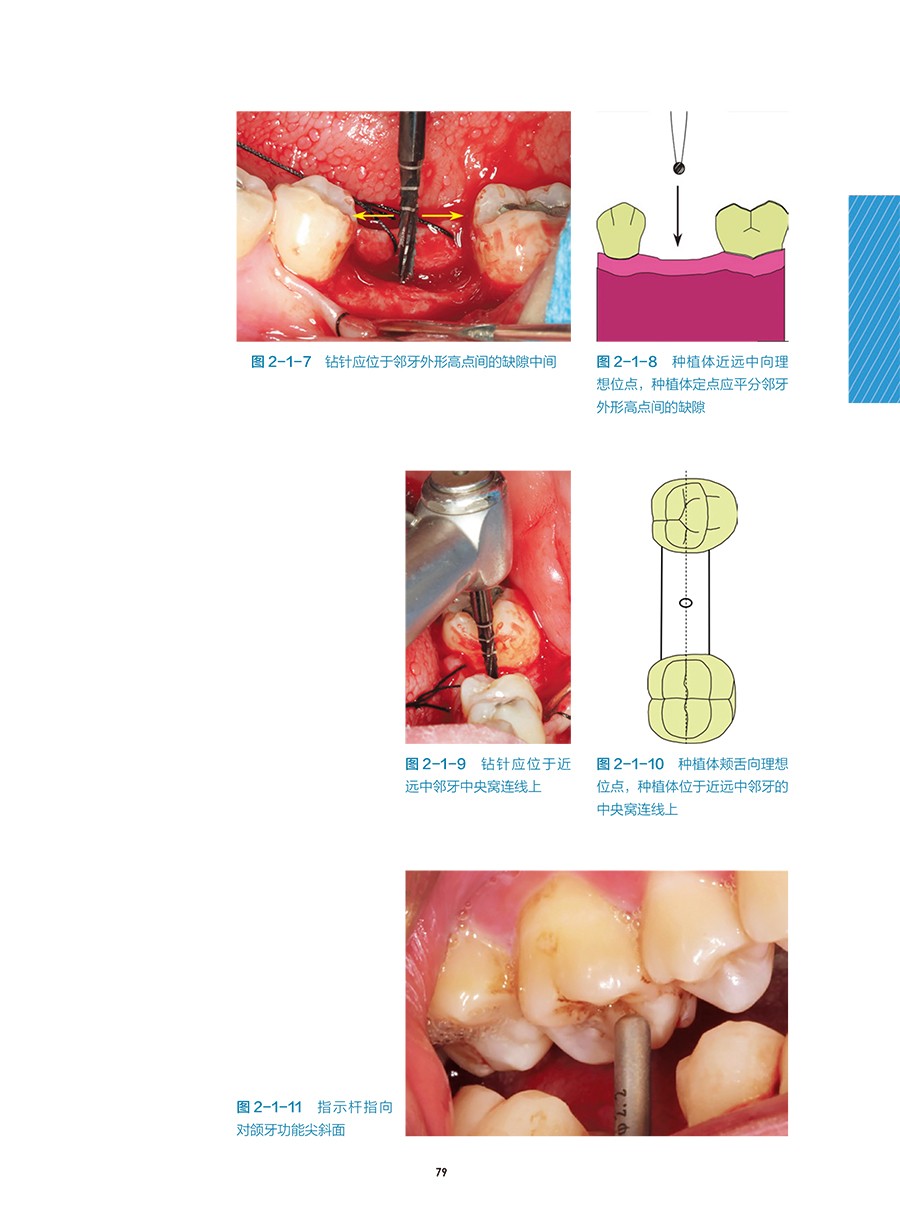

三、 定點和定軸向 / 77